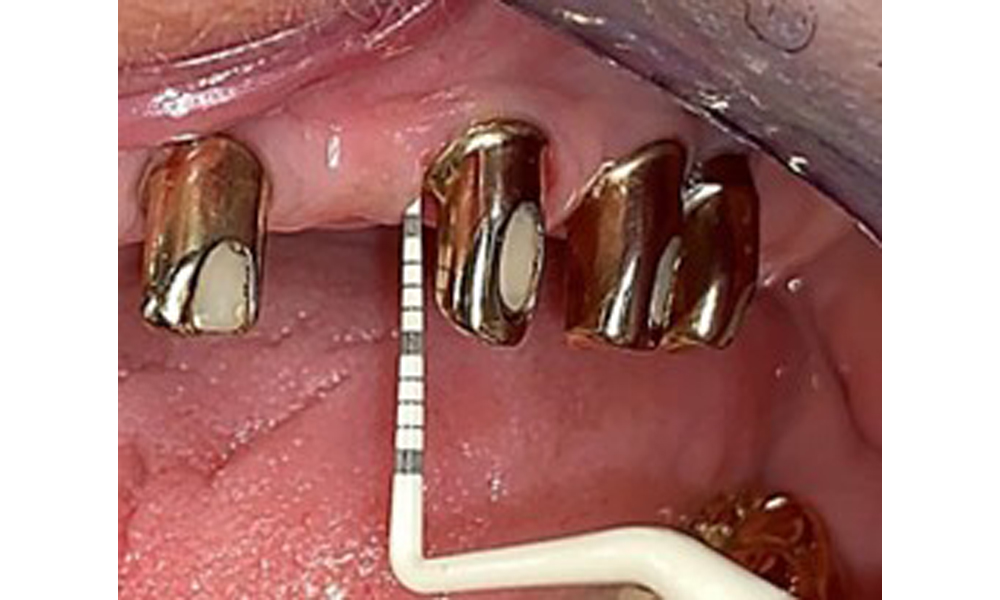

Probing implant 23 at a probing depth of 4 mm using a plastic probe, showing negative BOP findings and a hyperplastic papilla.

Fig. 6: Probing implant 23 at a probing depth of 4 mm using a plastic probe, showing negative BOP findings and a hyperplastic papilla.

The periodontal status should be thoroughly examined once a year. This examination provides comprehensive documentation of the periodontal and implant findings, including pocket depths, periodontal recession and furcation involvement. This will ensure a rapid response to any potential progression of the mucositis, gingivitis, periodontitis or peri-implantitis. Implant probing using a plastic probe is recommended. In the present case, a mesial probing depth of 4 mm was detected mesial to implant 23. No suppuration or bleeding was detected, indicating the absence of peri-implantitis.